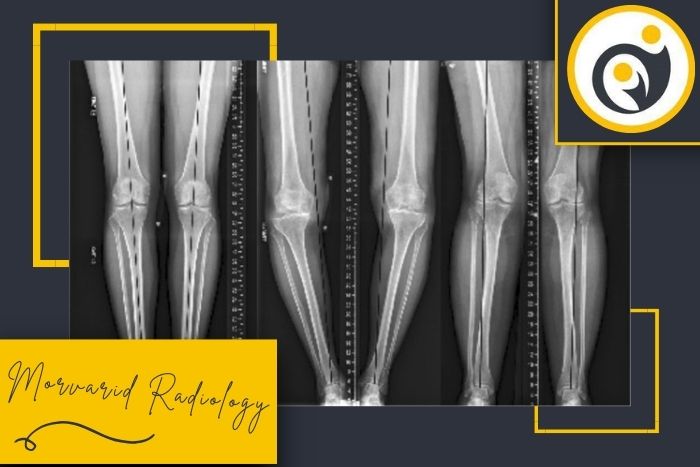

استفاده از دستگاههای دیجیتال نسل جدیدکیفیت بالای تصاویر و نمایش دقیق محور پا باعث میشود تشخیص و ارزیابی پزشکان با اطمینان بیشتری انجام شود.

تهیه عکس در حالت ایستاده برای بررسی واقعی محور اندام

عکسهای الایمنت ویو در مروارید ری طبق استانداردهای ارتوپدی و در وضعیت صحیح ایستاده گرفته میشود تا نتیجه کاملاً دقیق و قابل اعتماد باشد.